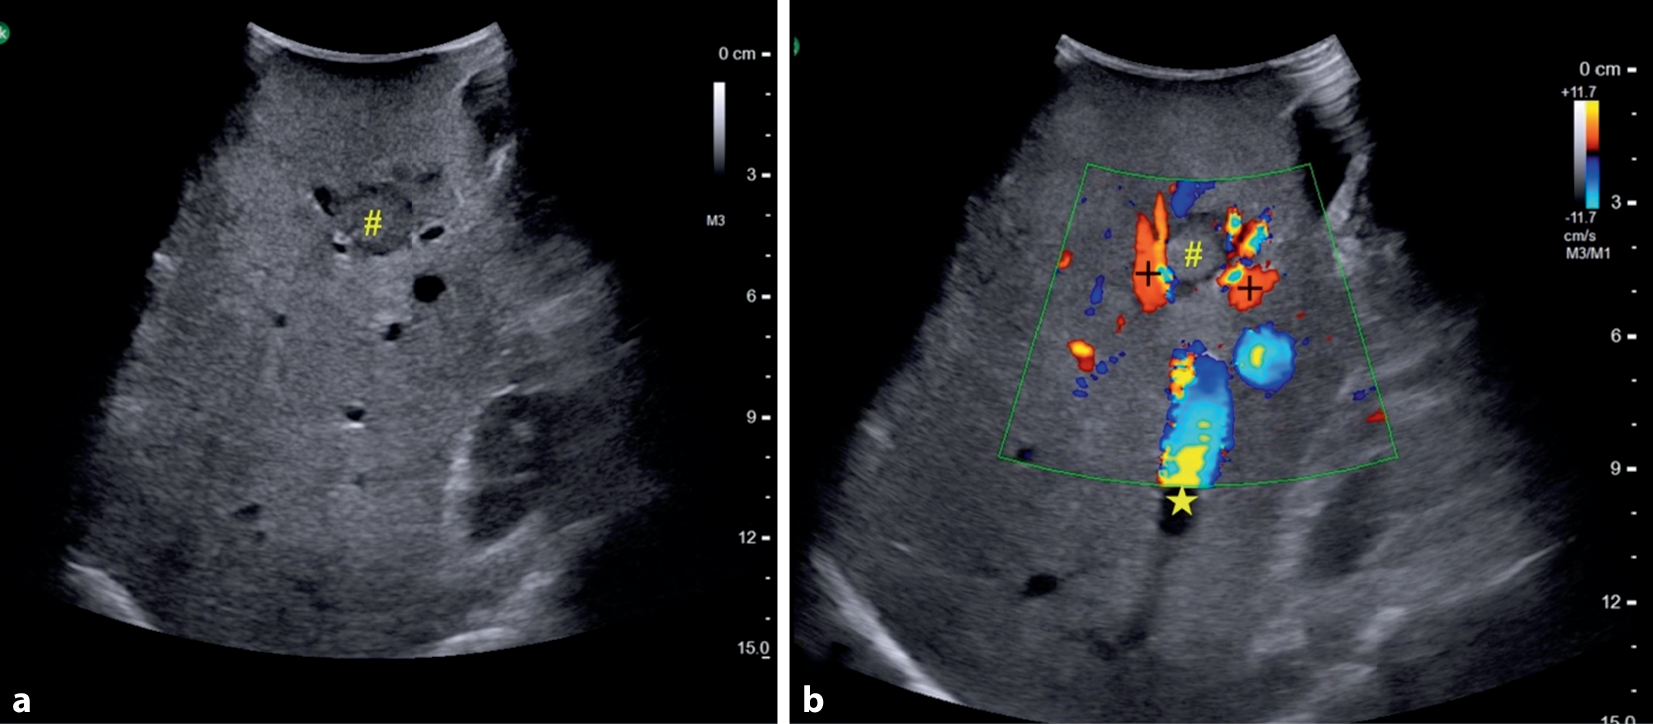

Im Rahmen eines Paradigmenwechsels in der Leberchirurgie orientiert sich die Resektion von kolorektalen Lebermetastasen zunehmend nicht mehr an anatomischen Segmentgrenzen, sondern primär an der individuellen Gefäßversorgung. Ziel ist eine maximal parenchymsparende Resektion, bei der möglichst wenig gesundes Lebergewebe entfernt wird [22, 24]. Der intraoperative Ultraschall (IOUS) spielt hierbei eine zentrale Rolle, da er die präzise Darstellung der Tumorlage in Relation zu den Gefäßstrukturen ermöglicht (s. Abb. 1). Dies unterstützt nicht nur die onkologische Radikalität, sondern auch eine gezielte, gefäß- und somit parenchymschonende Resektionsführung.

Abb. 1

Intraoperative Lebersonographie einer kolorektalen Lebermetastase im Segment 5, 6‑MHz-Konvex-Schallkopf zur Beurteilung des portalvenösen bzw. venösen Gefäßbezugs vor Resektion. # Lebermetastase, + rechte Portalvene, * rechte Lebervene. a zeigt den intraoperativen Ultraschall einer Lebermetastase inmitten echoleerer Strukturen ohne deren Art zu bestimmen1b erlaubt mit Hilfe der FKDS eine eindeutige Zuordnung der Strukturen mit Bezug zur Metastase